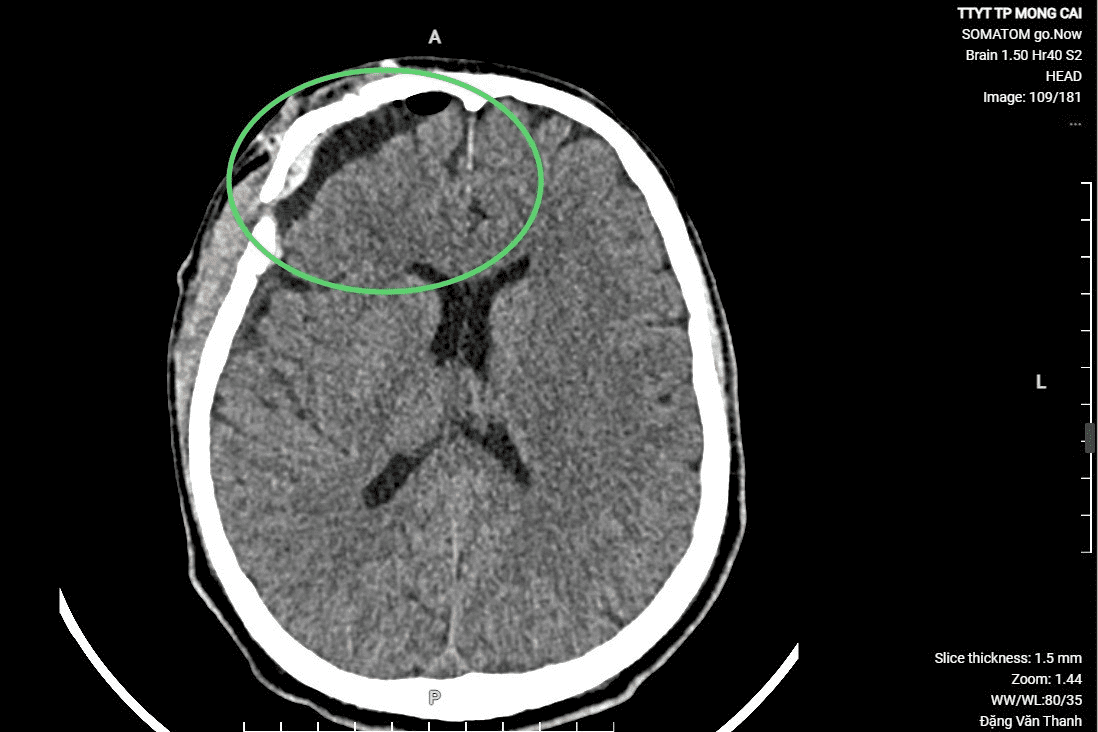

Hình ảnh chụp CT trước và sau khi phẫu thuật

Bệnh nhân được tiến hành phẫu thuật mở hộp sọ, lấy máu tụ trong não, cầm máu, sau hai ngày phẫu thuận, bệnh nhân tỉnh, không liệt, đã ngồi dậy bắt đầu tập phục hồi chức năng. Sau 7 ngày, bệnh nhân đã hoàn toàn tỉnh táo, bình phục gần như hoàn toàn.